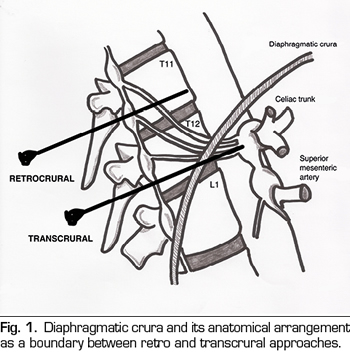

Diaphragmatic crura will determine anatomically whether the blockade performed represents a true celiac plexus block or if it is a splanchnic nerves block (Figure 1). If the tip of the needle is placed after the crura, the splanchnic nerves will be blocked. The needles arranged at the level of the vertebral body of T11 will always be behind the crura. Below this level, the crura becomes posterior and it is inserted into the vertebral bodies of T12 and L1. At this level, the needles can be placed both anterior and posterior to crura. The classic approach of Kappis (12) of needle positioning at the anterior edge of the vertebral body usually results in a retrocrural block, demonstrated in subsequent studies on dead bodies with CT scan (13). To achieve a true block anterior to crura, the needle must be moved further so that it is anterior to the abdominal aorta.

Once this issue is clarified, we can classify percutaneous approaches as follows (Figure 2):

Transcrural approach: the most commonly used for the blockage of the celiac plexus (Figure 3). The patient is placed in prone position, identifying the vertebral body L1 and advancing a needle on each side, approximately 7.5 cm from the midline, until it crosses the diaphragmatic crura and blocks the plexus.

Retrocrural approach: an approach that has been classically described for both the celiac plexus block (at the L1 level) and for the splanchnic nerves. In the pure retrocrural approach, the patient is placed in prone position and the vertebral bodies of T11 and T12 are located, advancing the needles to the anterior third of these bodies and thus blocking the splanchnic nerves.